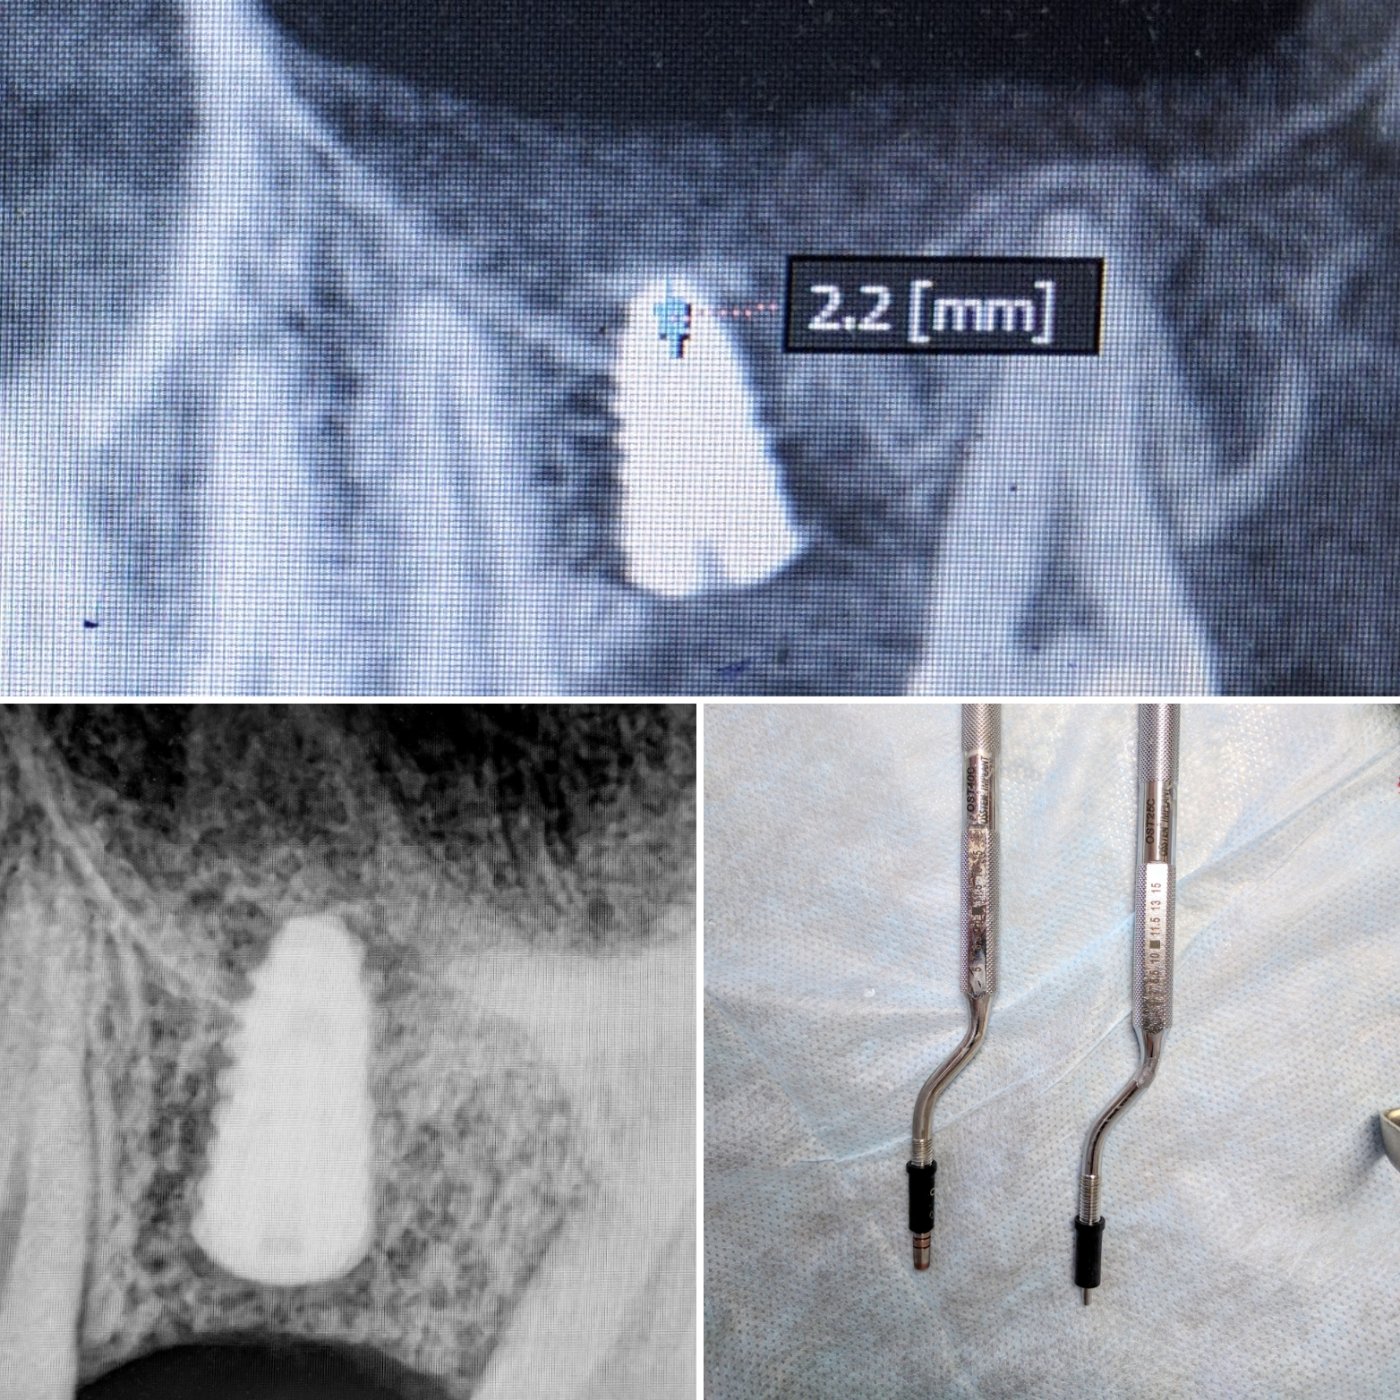

Из навыков: открытый и закрытый синус лифтинг, одномоментная имплантация , расщепление альвеолярного гребня, sausage technique и другая направленная костная регенирация, опыт в работе с титановыми сетками на имплантатах Osstem система Smart Builder, мягкотканная пластика десны, пародонтологические операции. Удаление зубов любой сложности, чтение клкт (3D) и составления рационального плана лечения, стремление расти и развиваться профессионально!